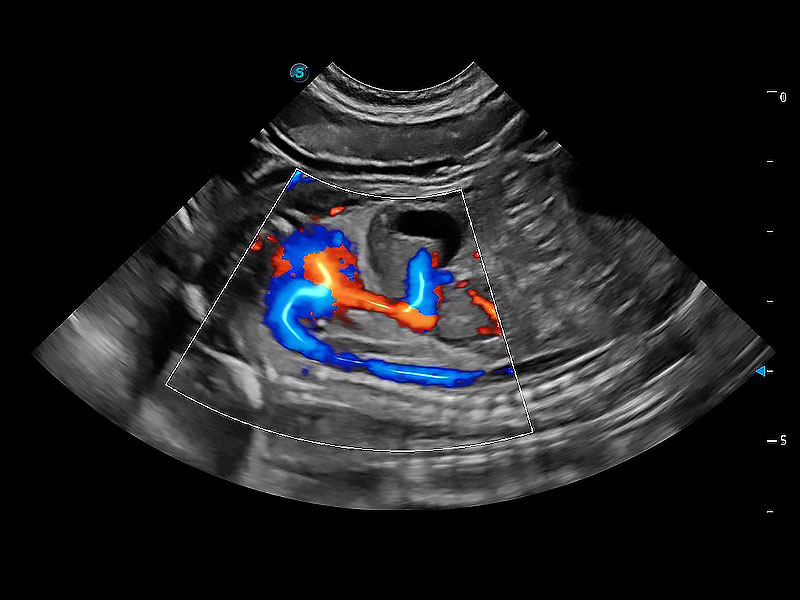

在传统二维血流成像的基础上,呈现血流的立体感,具有动感的生命力之美。即便是微小的血管也能轻松应对,提高了血流的视觉敏感性。

ProPet 80 配备了丰富的心脏探头群、先进的成像技术和专业的心脏测量工具,可帮助动物医生为不同体型和生理结构的动物提供心脏和心肌功能的全面评估。